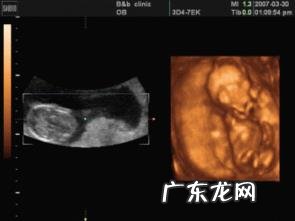

孕妇做个四维彩超要多长时间?

大排畸四维彩超是在孕22-28周需要做的一项重要检查,做四维彩超要提前预约,一般花费时间在15-30分钟左右 。具体需要多长时间,是因人而异的,有的孕妈妈仅仅需要十几分钟就可以完成检查,而有的孕妈妈则需要长达一个小时左右或者好几次(可能一天做几次,也可能连着几天去做)才能检查完毕 。

做四维彩超需要多长时间受胎儿是否配合,医生经验,孕妈妈肚皮脂肪厚度来决定 。